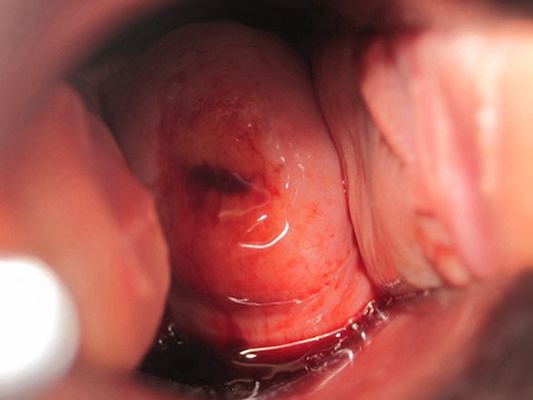

子宮肥大圖片

子宮肥大圖 (7)

子宮肥大圖 (8)

子宮肥大圖 (9)